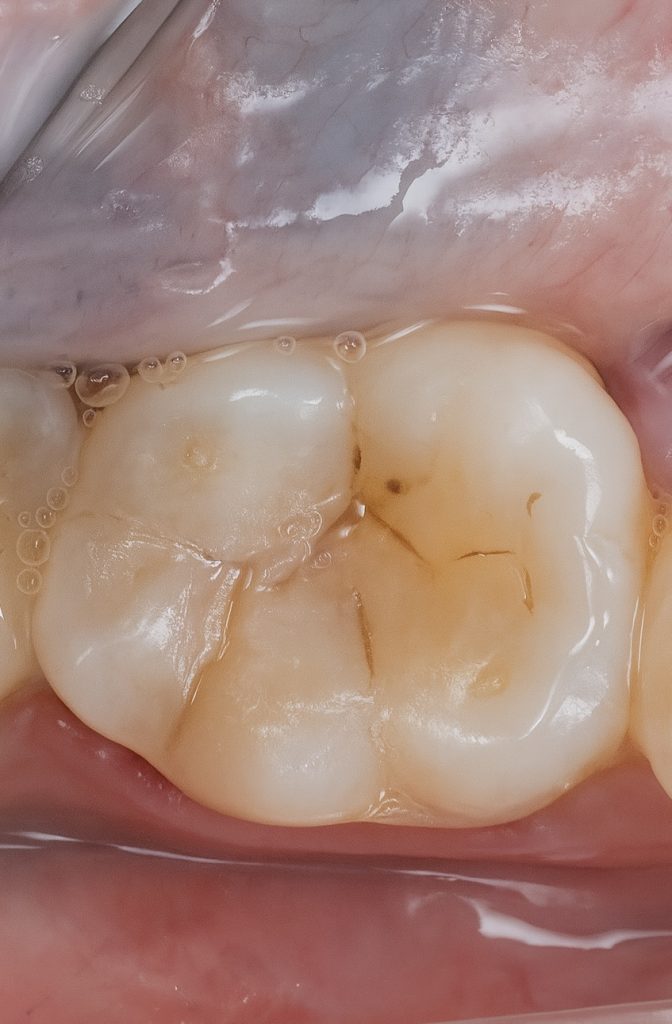

Selective enamel etching with 37 % phosphoric acid (15 s) was followed by a universal adhesive (3M Scotchbond Universal) applied actively for 20 s, air-thinned, and light-cured (Fig 2). This ensured optimal micro-retention and hybrid-layer formation.

- Fig 2: Cavity after caries removal and selective etching.